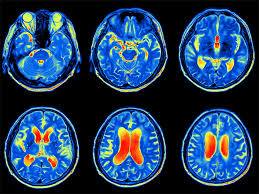

نقشه مغزی یا (QEEG) چیست؟

تحول الکتروانسفالوگرافی کمی: نسل نوین نقشه‌برداری مغز برای روان‌پزشکی فردمحور

الکتروانسفالوگرافی کمی(QEEG) یا نقشه مغزی ، یکی از به روزترین و پر استفاده‌ترین ابزارهای تصویر برداری عملکردی از مغز می‌باشد. در نقشه مغزی ، با استفاده از دستگاه QEEG و بسته به نوع اختلال، عملکرد نواحی سطحی و عمقی مغز مورد بررسی و ارزیابی قرار می‌گیرد و می‌تواند اطلاعات زیادی را در رابطه با نوع اختلال، علائم ناشی از اختلال و انتخاب درمان مناسب در اختیار پزشک قرار دهد.